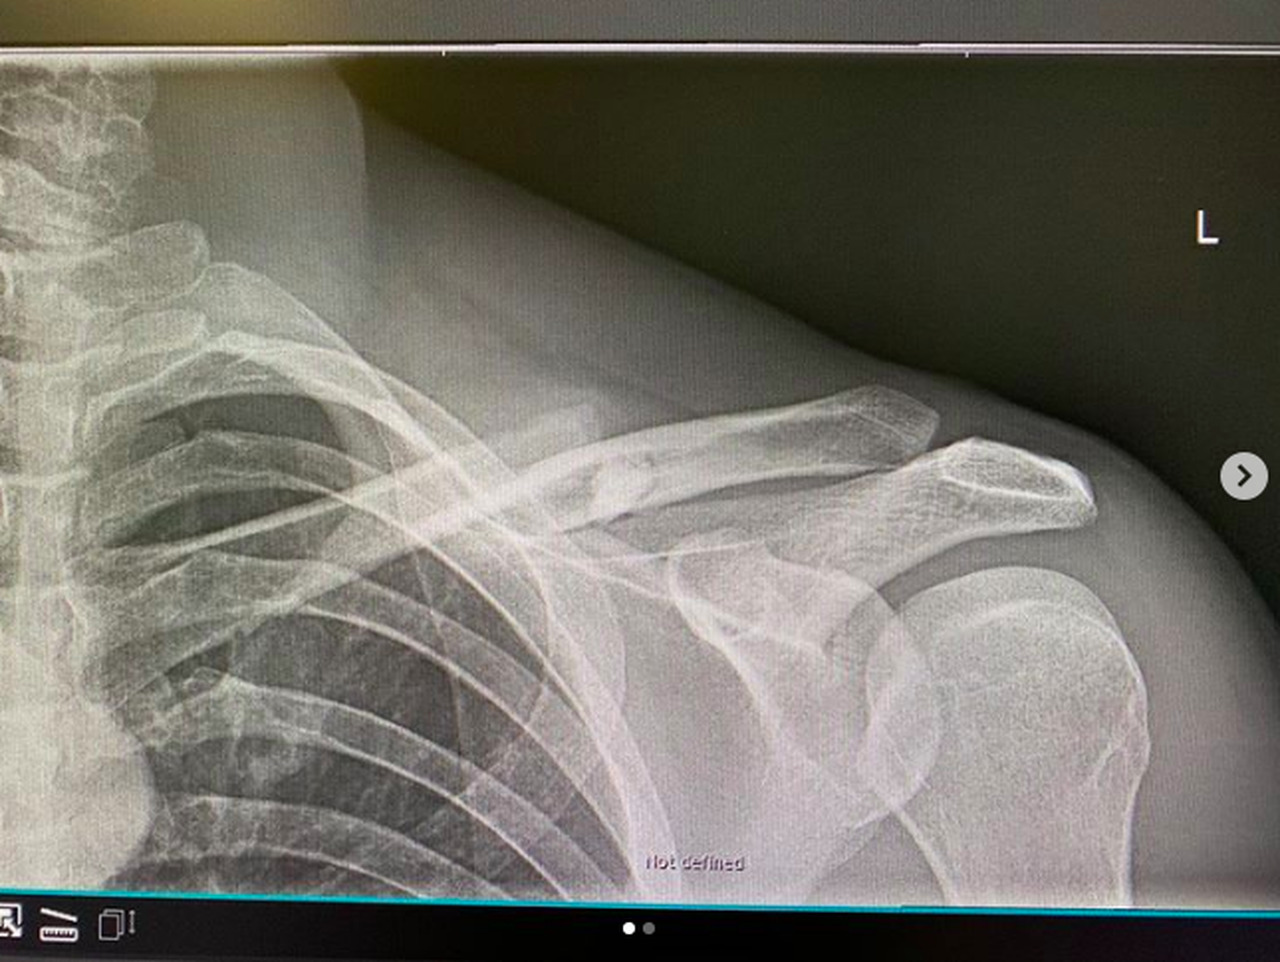

Kienle divulgou em sua conta do Instagram que, duas horas e meia depois do acidente já passava por cirurgia para a correção da fratura.

Abaixo, confira o post do alemão comunicando o acidente: